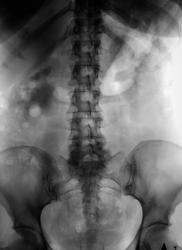

Пациентка направлена на внутривенную урографию. Какие будут мнения?

Слабое контратирование левой почки, мочеточник прослеживается до уровня крестца. Тень в проекции дистального отдела левого мочеточника, возможно конкремент.

Согласен. Просмотрел. Значит, остаётся гидронефроз справа, возможно стриктура или врождённое высокое отхождение мочеточника.

Признаки нарушения оттока из правой ЧЛС симнительной этиологии))

На томограмах складывается ощущение, что справа видна значительно расширенная тень мочеточника? Особенно, если сравнить две половины. Точно сказать нельзя, потому что там m.psoas подобной конфинурации проходит.

Врожденное сужение ЛМС справа...вот и все....)))), а все остальное - следствие.